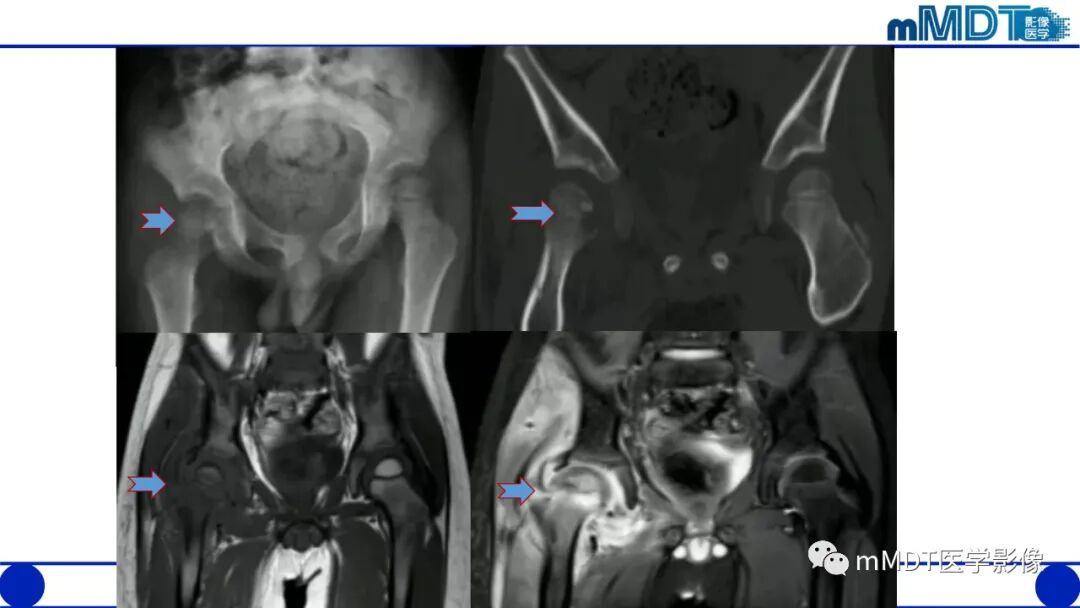

1.平片、CT:活动期表现骨质疏松,股骨头和转子间弥漫性骨密度减低,股骨头软骨下骨皮质吸收,髋臼受累程度轻,无骨侵蚀或破坏,关节间隙保持正常。

2.MRI:股骨头至转子间在T1WI低信号,T2WI及脂肪抑制像呈均匀一致高信号,无局灶性改变,多伴髋关节积液,周围肌肉层次清晰,随访多于6-10个月内恢复正常,无后遗症。